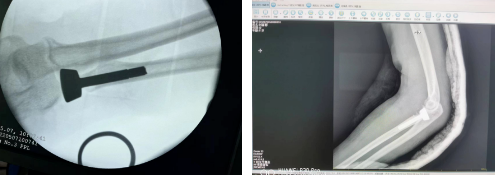

此次手术由骨伤科主任周建全、主任医师罗斌和手术室工作人员共同完成。术后患者患侧肘关节功能及前臂旋转功能改善,恢复很好,患者和家属都非常满意。

该技术不仅可使患者肘关节伸屈、前臂旋转功能不受限,还因有假体填充维持了桡骨生理长度,防止桡骨干上移,减少了并发症的发生,且患者术后即可开始功能活动和康复锻炼。